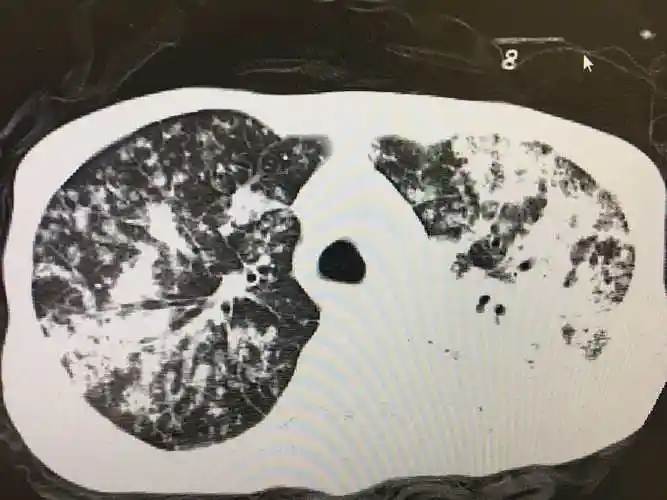

一例重症肺结核的资料

图片尺寸 2666x2000